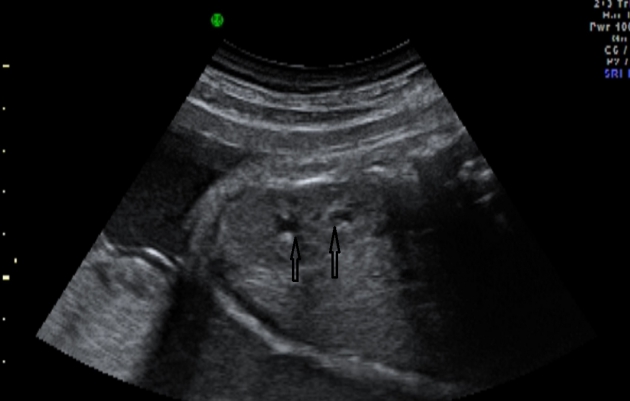

3/3 Геннадьевич?Впр: двухстворчатый аортальный клапан без стеноза. Омфаломезентериальная киста.

Почему киста пуповины?